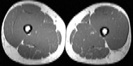

Visible Human male: Sectio transversalis 2070

CT

NMR

Pd / T2 \ T1